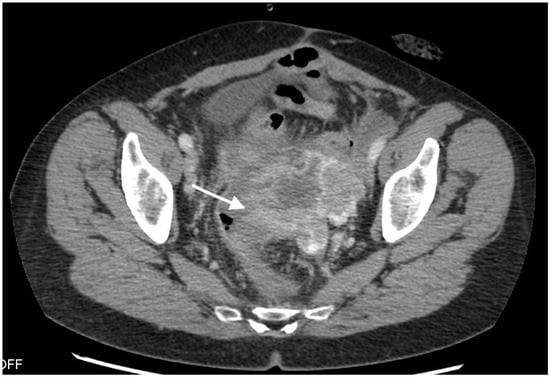

Figure 3.

Images of a 57-year-old patient with high-grade serous ovarian cancer recurrence. Computed tomography shows large cystic-solid pelvic tumor with fluid/gas level and adjacent rectum as indirect sign of fistula.

The median diameter of the relapsed tumor was 89 mm (range 36–130 mm). In all cases, fistulas formed between the tumor and large bowel. In three cases, fistulas formed between the rectum, including two between the sigmoid colon, one sigmoid and descending colon, one between the cecum and ascending colon, and one between the sigmoid colon and left ureter. On CT, in all cases, the fistulas were not directly visible, with only indirect signs of the fistula observed, such as infiltration of the intestine by the tumor, which we observed as vanishing of the fatty tissue between the tumor and the description of the intestinal wall, disruption of the intestinal wall, or the presence of gas in the tumor. In five patients, we observed thickening of the intestinal wall associated with a fistula (Figure 1, Figure 2 and Figure 3).

On computed tomography, we observed only indirect imaging signs of fistulas, such as infiltration of the intestine by the tumor, which we observed as vanishing of the fatty tissue between the tumor and the intestine, disruption of the intestinal wall, and gas in the tumor. Computed tomography’s limitation is evident when evaluating local tumor spread due to its lower soft tissue resolution. In other studies, CT was very useful for diagnosis, revealing indirect signs of fistulas, such as obvious thickening of the tumor wall and an air-fluid level within the tumor, suggesting that the ovarian tumor might have communication with the digestive tract; however, they also did not observe fistulas directly [11].